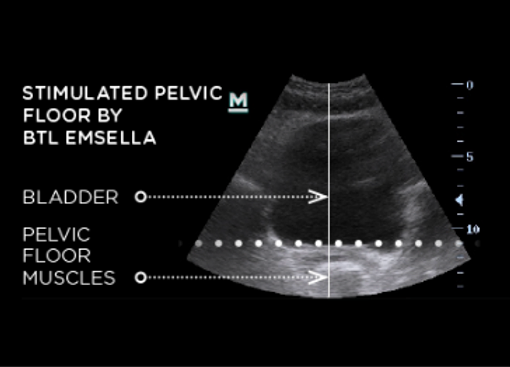

Esmella After Ultrasound Image

EMSELLA® utilizes electromagnetic energy to deliver thousands of supramaximal pelvic floor muscle contractions in a single session. These contractions re-educate the muscles of incontinent patients.